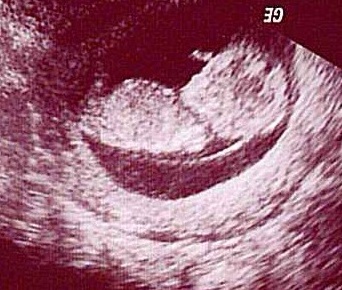

Amikor megtudtam, hogy babátok lesz, veletek örültem, és ez most is így van, de iszonyúan fáj, hogy amíg ti életetek legnagyobb öröméről beszéltek, én azon aggódom, hogy ugye nekem is lehet majd babám... Talán önzés, talán azért van ez, mert mások vagyunk.

) (nem számonkérés vagy hibáztatás) annak a nehézségét, aki nem tart ott... (Remélem, ez sem lett bántó!) Mert ez egy olyan állapot, amit szerintem csak az ért/érez, aki elveszítette a babáját, de még nincs neki azóta... (Ráadásul, ha van min izgulnia...) Nektek ez egy átmeneti állapot volt, túl vagytok rajta, így van ez rendjén. Remélem, nekünk is csak átmeneti lesz!!!